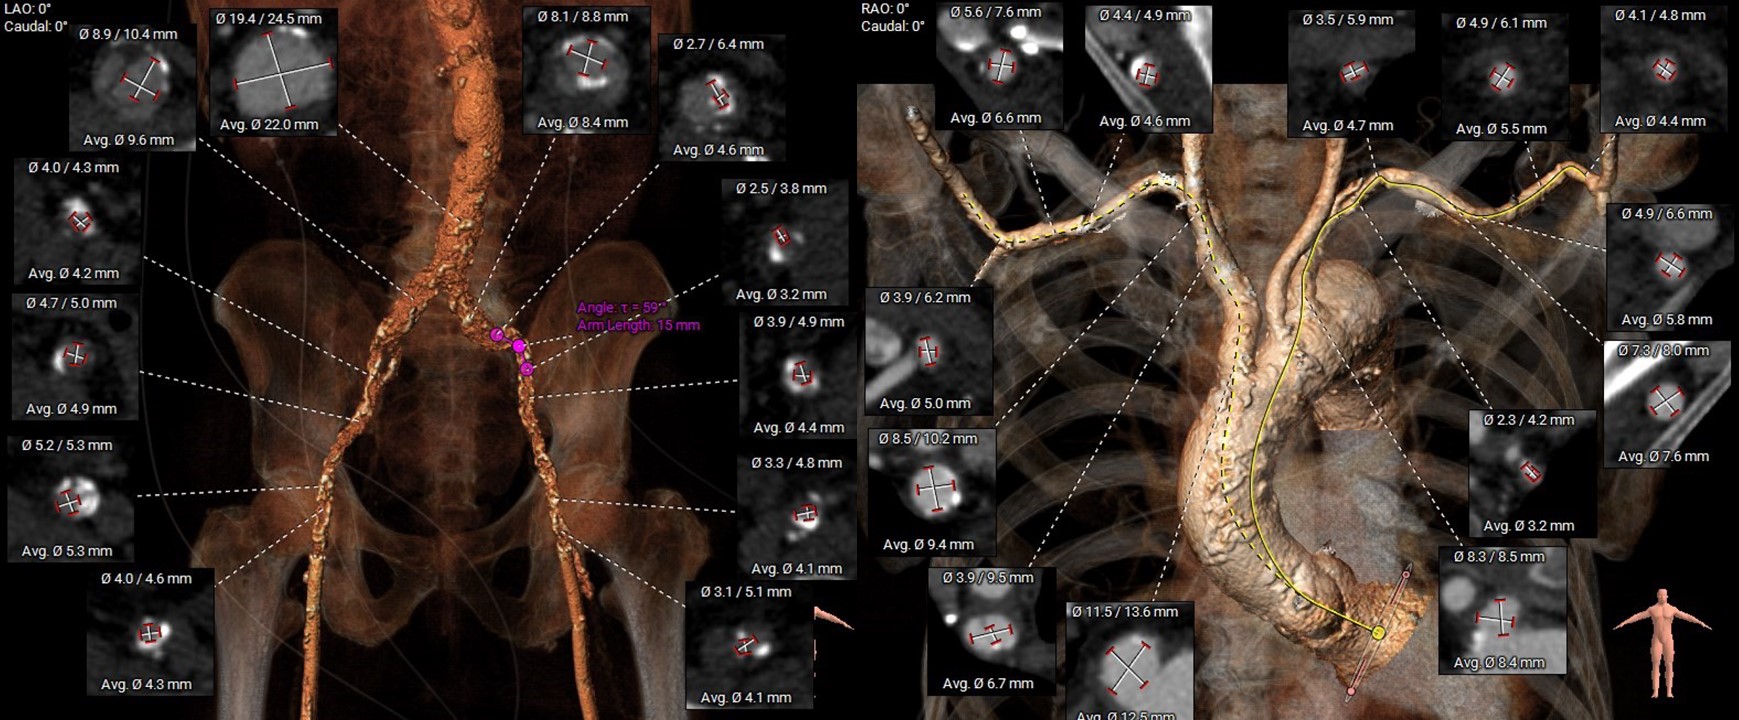

However, multislice CT scan revealed severe stenosis and calcific change in bilateral femoral arteries, making the transfemoral arterial approach unfeasible. Alternative access sites, including bilateral carotid and axillary arteries, were also not feasible. Although there was severe calcification in the abdominal aorta, the transcaval approach targeting a calcium-free segment of the aorta at the L3 level represented barely the last resort for carrying out TAVI procedures.

The transcaval approach starts with descending abdominal aortography. A 7-F renal double curve guide catheter which was advanced through the right femoral vein. An Astato wire along with a CXI microcatheter were advanced through the catheter to the indexed L3 level for transcaval puncture with the distal end of the Astato guidewire connecting with an electrosurgery pencil. After the Astato guidewire cross the vena cava and the adjacent aortic wall, the Asatato-CXI system was then captured by a 25 mm Gooseneck snare placed at the corresponding aortic level through left femoral atery, and sent upward to the thoracic aortic level. The Asatato wire was exchanged for a Lunderquist guidewire, through which an 20 French long sheath was advanced through RFV to the abdominal aorta. Standard TAVI procedures employing a Navitor 27 mm transcatheter heart valve were then performed through this vena-aortic connection facilitated by LV on-wire pacing. At the end of the procedure, an Amplatzer Duct Occluder was deployed to close the aorto-caval tract, with post-procedural angiography confirming a patent fistula with cruciform contrast flow around the neck of the occluder but with contrast returning to the cava. After careful examination, there was no extravasation on the digital subtraction angiogram. The next day, a follow-up angiogram of the aorto-caval fistula was performed, which revealed a patent fistula but without extravasation. The patient is doing well during one year of follow-up.